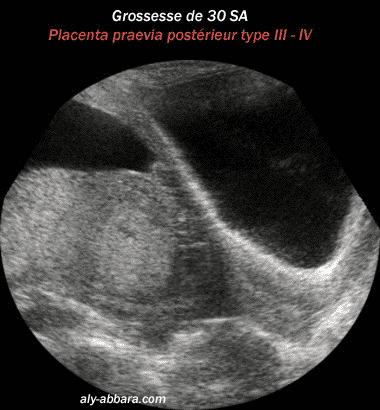

Placenta prævia, postérieur recouvrant

l'orifice interne du col utérin

(Type III - IV selon BESSIS R, BRIGNON

C, SCHNEIDER L. 1976)

à 30 semaines d'aménorrhée

Cette image montre l'insertion anormale

du placenta ; il s'insère sur la paroi postérieure du segment

inférieur,

et recouvre l'orifice interne du col utérin et la moitié de

la paroi antérieure du segment inférieur